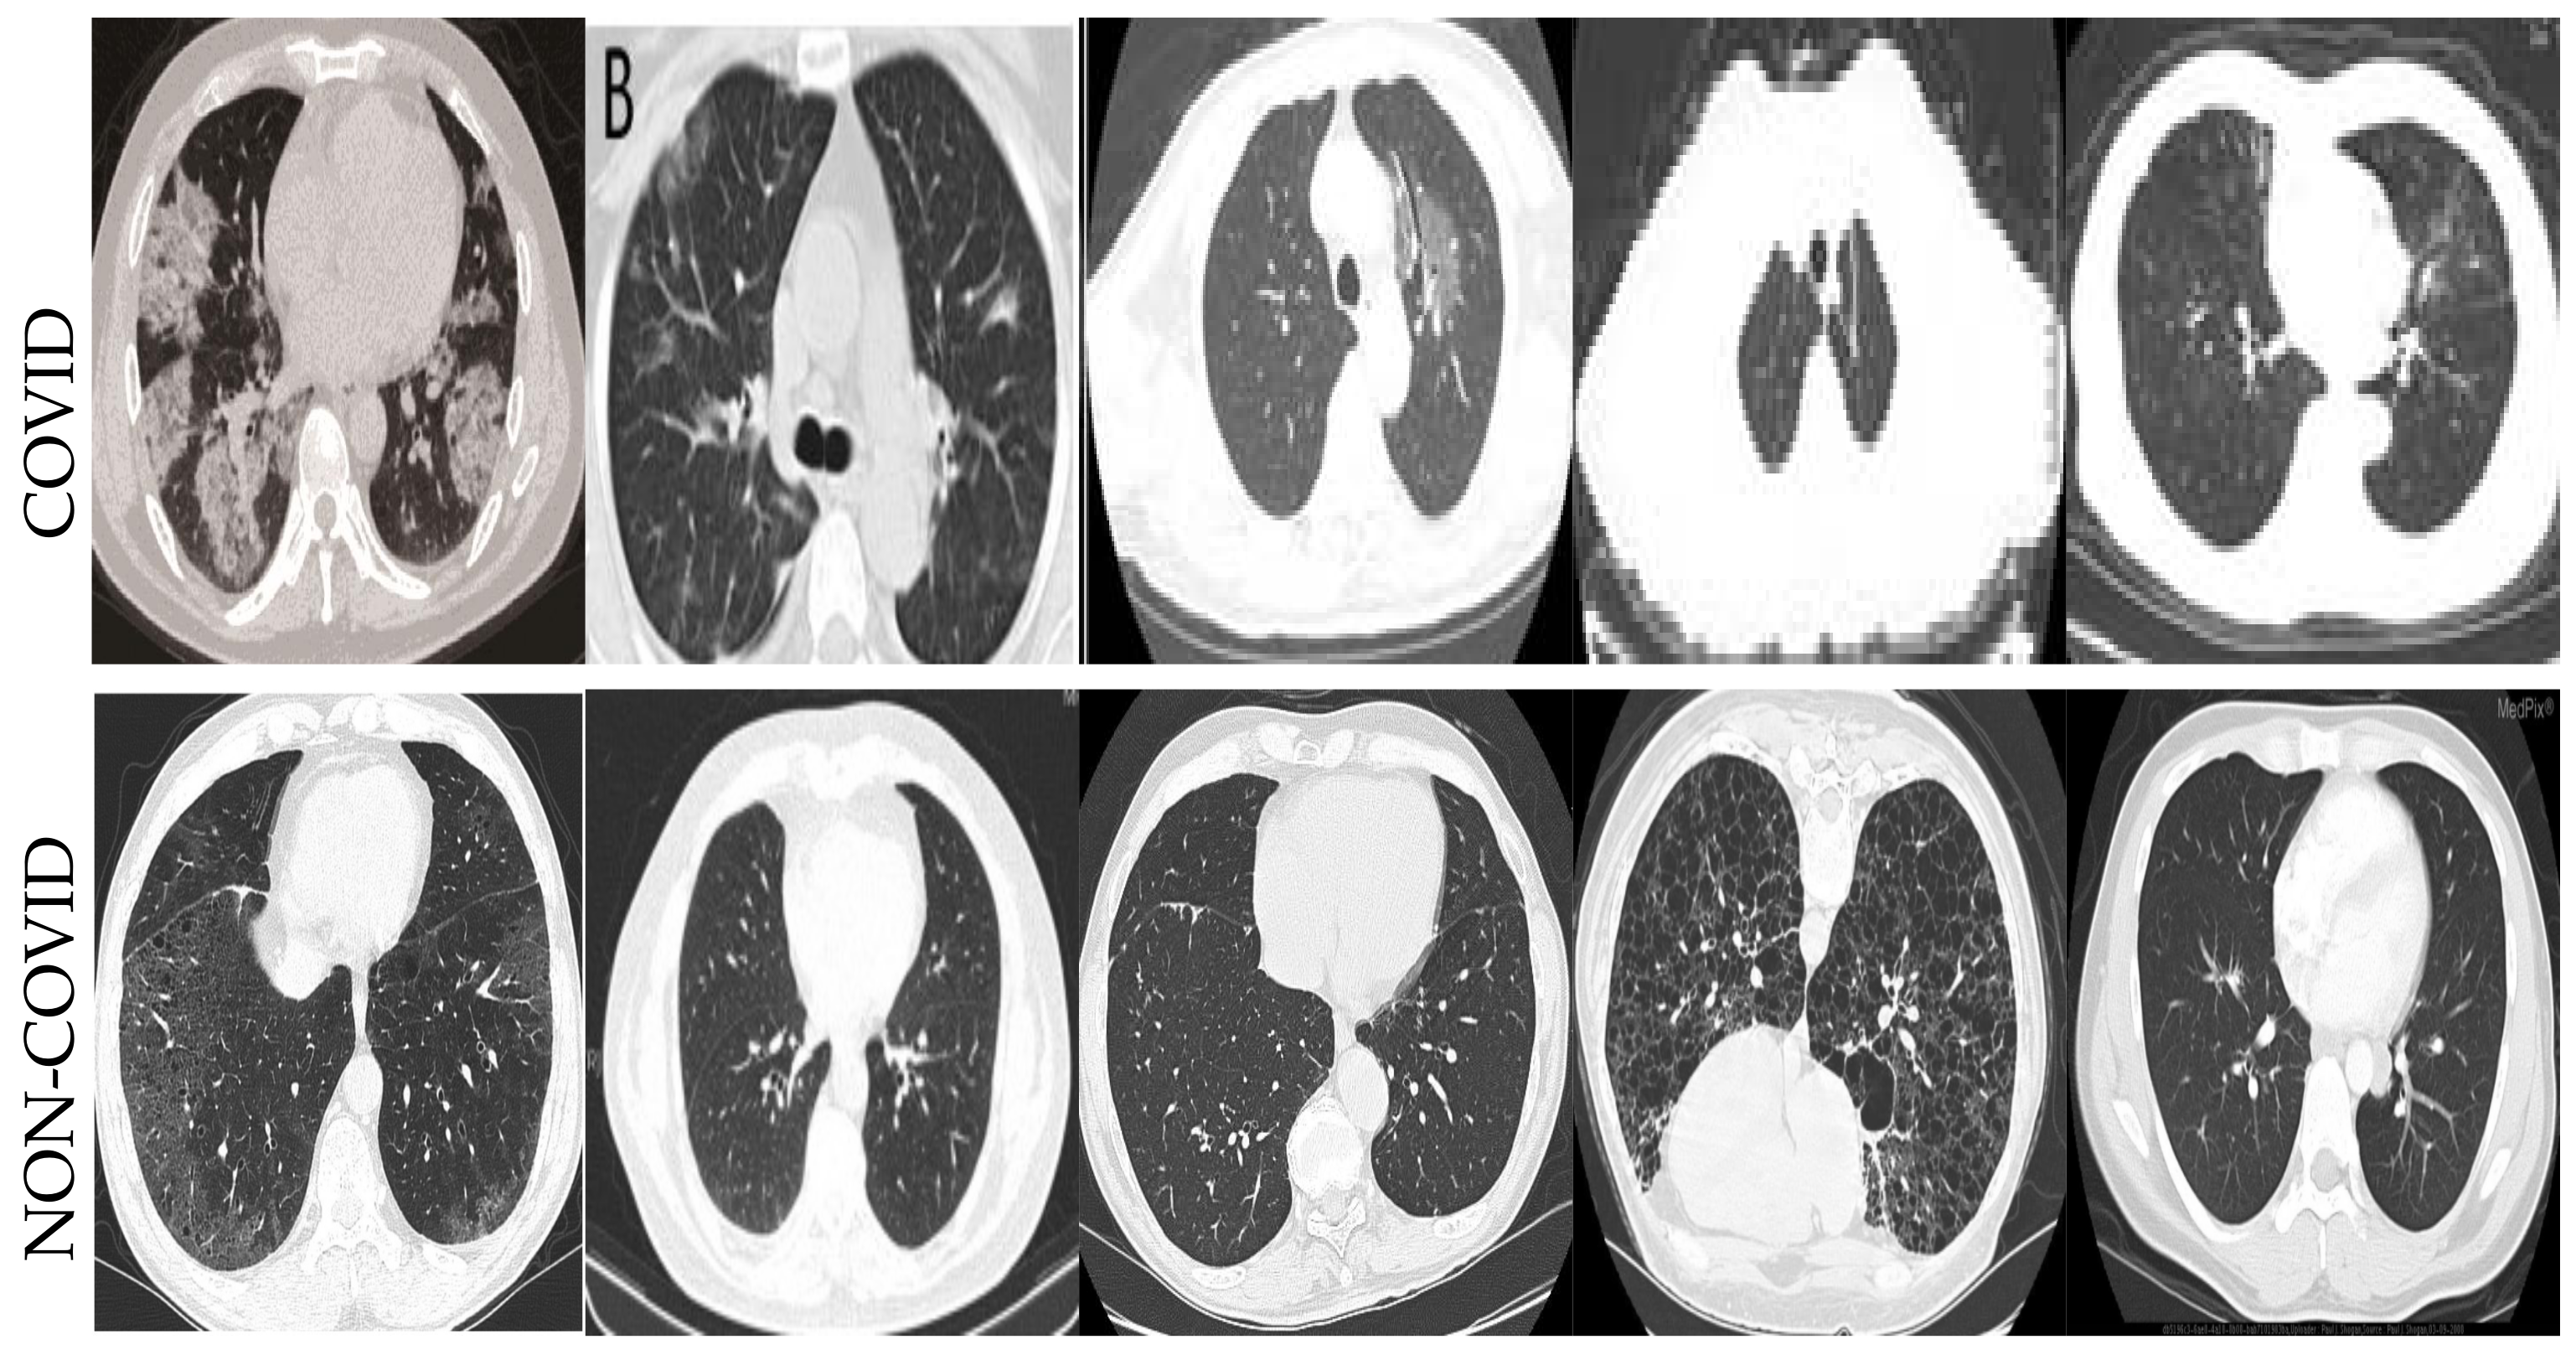

- We employ the deep learning algorithms for COVID-19 datasets to detect infection in the CT and X-ray images;

4.3. Metrics